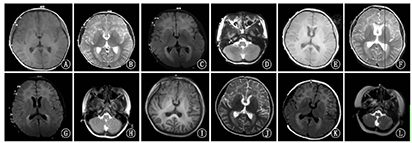

例3,女,32岁。29岁时由于其女儿(先证者)因"反复惊厥发作,发育迟滞"诊断为Ⅰ型AxD患儿,进行基因测序时发现先证者GFAP杂合突变(c.236G>A, p.Arg79His)遗传自母亲。其自幼智力运动发育正常,末次随访时无运动认知倒退,无癫痫发作、构音障碍、饮水呛咳、吞咽困难等表现。头颅MRI(29岁)示双侧脑室前后角旁深部白质T1WI低信号、T2WI高信号、T2FLAIR高信号,右侧枕叶皮层下白质小片状异常信号,延髓和颈髓上段较细、胼胝体体部薄(图3)。

注:A~C分别为T1加权像、T2加权像及T2液体衰减反转恢复序列图像轴位;D为T1加权像矢状位 A-C:Axial T1 weighted imaging,T2 weighted imaging and T2 fluid attenuated inversion recovery imaging showed signal abnormalities;D:sagittal T1 weighted imaging